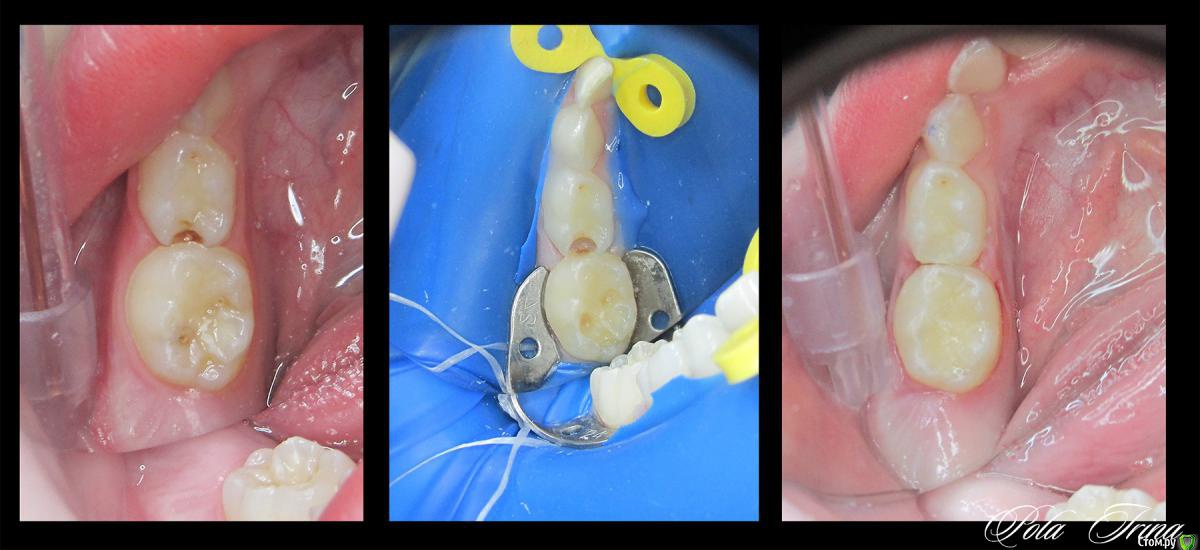

CRAZYDUCK Опубликовано 21 сентября, 2015 Поделиться Опубликовано 21 сентября, 2015 (изменено) http://s020.radikal.ru/i713/1509/6e/6af33d606cc5.jpgСпасибо большое коллегам за советы по коффердаму ( особенно Танюше!), работать с коффердамом просто классно !!!! удобно и быстро , детям он тоже нравится, доктора , не бойтесь его осваивать ! Здесь правда мальчик "большой"- 6 лет, но все же - кариес 5.5 ,пульпит 5.4, сначала кламп поставила KSK для 5.5 зуба , потом платок , потом рамку , фото не очень много, но мне неудобно без ассистента , еще фотоаппарат долго "думает" почему-то.( снимок RVG 5.4, 5.5 до лечения).P.S. Лечила этого мальчишку в конце февраля ( кариес 8.4 и пульпит 8.5), были эти кариозные полости ( на 5.5 и 5.4 зубах уже тогда), но так как у меня срок родов был в марте , работать уже было тяжело и запись была большая , отправила их к коллеге ( лично его не знаю , но отзывы хорошие были), вот полечили они у этого доктора эти кариесы в мае , а в сентябре пришлось перелечить... Изменено 21 сентября, 2015 пользователем CRAZYDUCK 4 Ссылка на комментарий